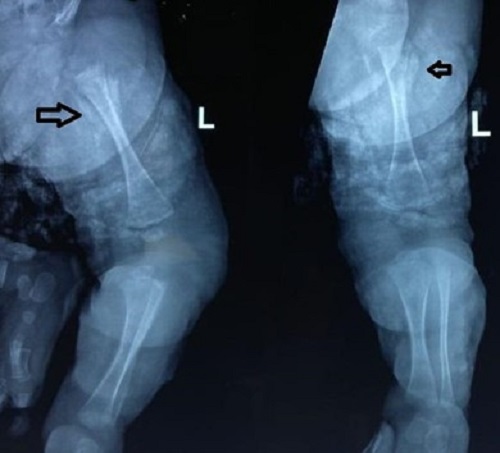

A 15-day-old male baby was admitted with swelling around the right shoulder joint, right knee, and right index finger for 3 days and associated fever for 2 days. There was no history of decreased movements at the shoulder and knee joints. The baby had term gestation and had respiratory distress at birth, kept in the NICU for 5 days on oxygen support—no h/o umbilical catheterization. On examination, the baby had tender swelling with fluctuation around the right shoulder joint. Blood investigations revealed TLC-27,000/uL (N-70%) and CRP-169 mg/L. X-rays of the right shoulder, right knee, and right index finger were normal. Incision and drainage of shoulder abscess was done. Blood culture and Pus culture both had MRSA growth. Inj. Vancomycin was given for 1 week and the baby was discharged on oral linezolid. But the child again got admitted 5 days after discharge, with swelling above the left knee. X-rays were repeated which revealed left distal femur osteomyelitis and right upper tibia extensive diaphyseal osteomyelitis (Fig. 3). Repeat TLC- 22,000/uL (N-56%) and CRP-70 mg/L. Surgical debridement was done. The baby received 4 weeks of i.v vancomycin and was discharged on an oral antibiotic (Linezolid).

Figure 3

(a) Extensive diaphyseal osteomyelitis in the upper end of the right tibia and (b) Rarefaction distal end of the left femur.